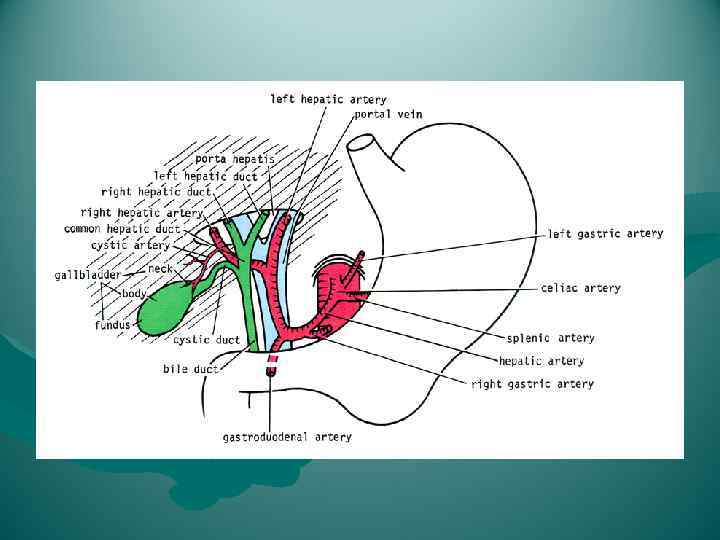

Lig. Hepatoduodenale Cлева печеночная артерия и ее ветви, справа — общий желчный проток и формирующие его общий печеночный и пузырный протоки, между ними и сзади — воротная вена, v. portae. В самом нижнем отделе связки проходят правые желудочные, a. et v. gastricae dextrae, и желудочно-двенадцатиперстные, a. et v. gastroduodenales, сосуды.

Lig. Hepatoduodenale Cлева печеночная артерия и ее ветви, справа — общий желчный проток и формирующие его общий печеночный и пузырный протоки, между ними и сзади — воротная вена, v. portae. В самом нижнем отделе связки проходят правые желудочные, a. et v. gastricae dextrae, и желудочно-двенадцатиперстные, a. et v. gastroduodenales, сосуды.

Кровь к печени поступает по двум системам: по воротной вене ( 70%) и по печеночной артерии (30%). Величина кровотока - 84 г на 100 г органа в минуту. Площадь поперечного сечения капилляров 400 м 2. Кровоток по воротной вене - 1, 5 л/м.

Кровь к печени поступает по двум системам: по воротной вене ( 70%) и по печеночной артерии (30%). Величина кровотока - 84 г на 100 г органа в минуту. Площадь поперечного сечения капилляров 400 м 2. Кровоток по воротной вене - 1, 5 л/м.